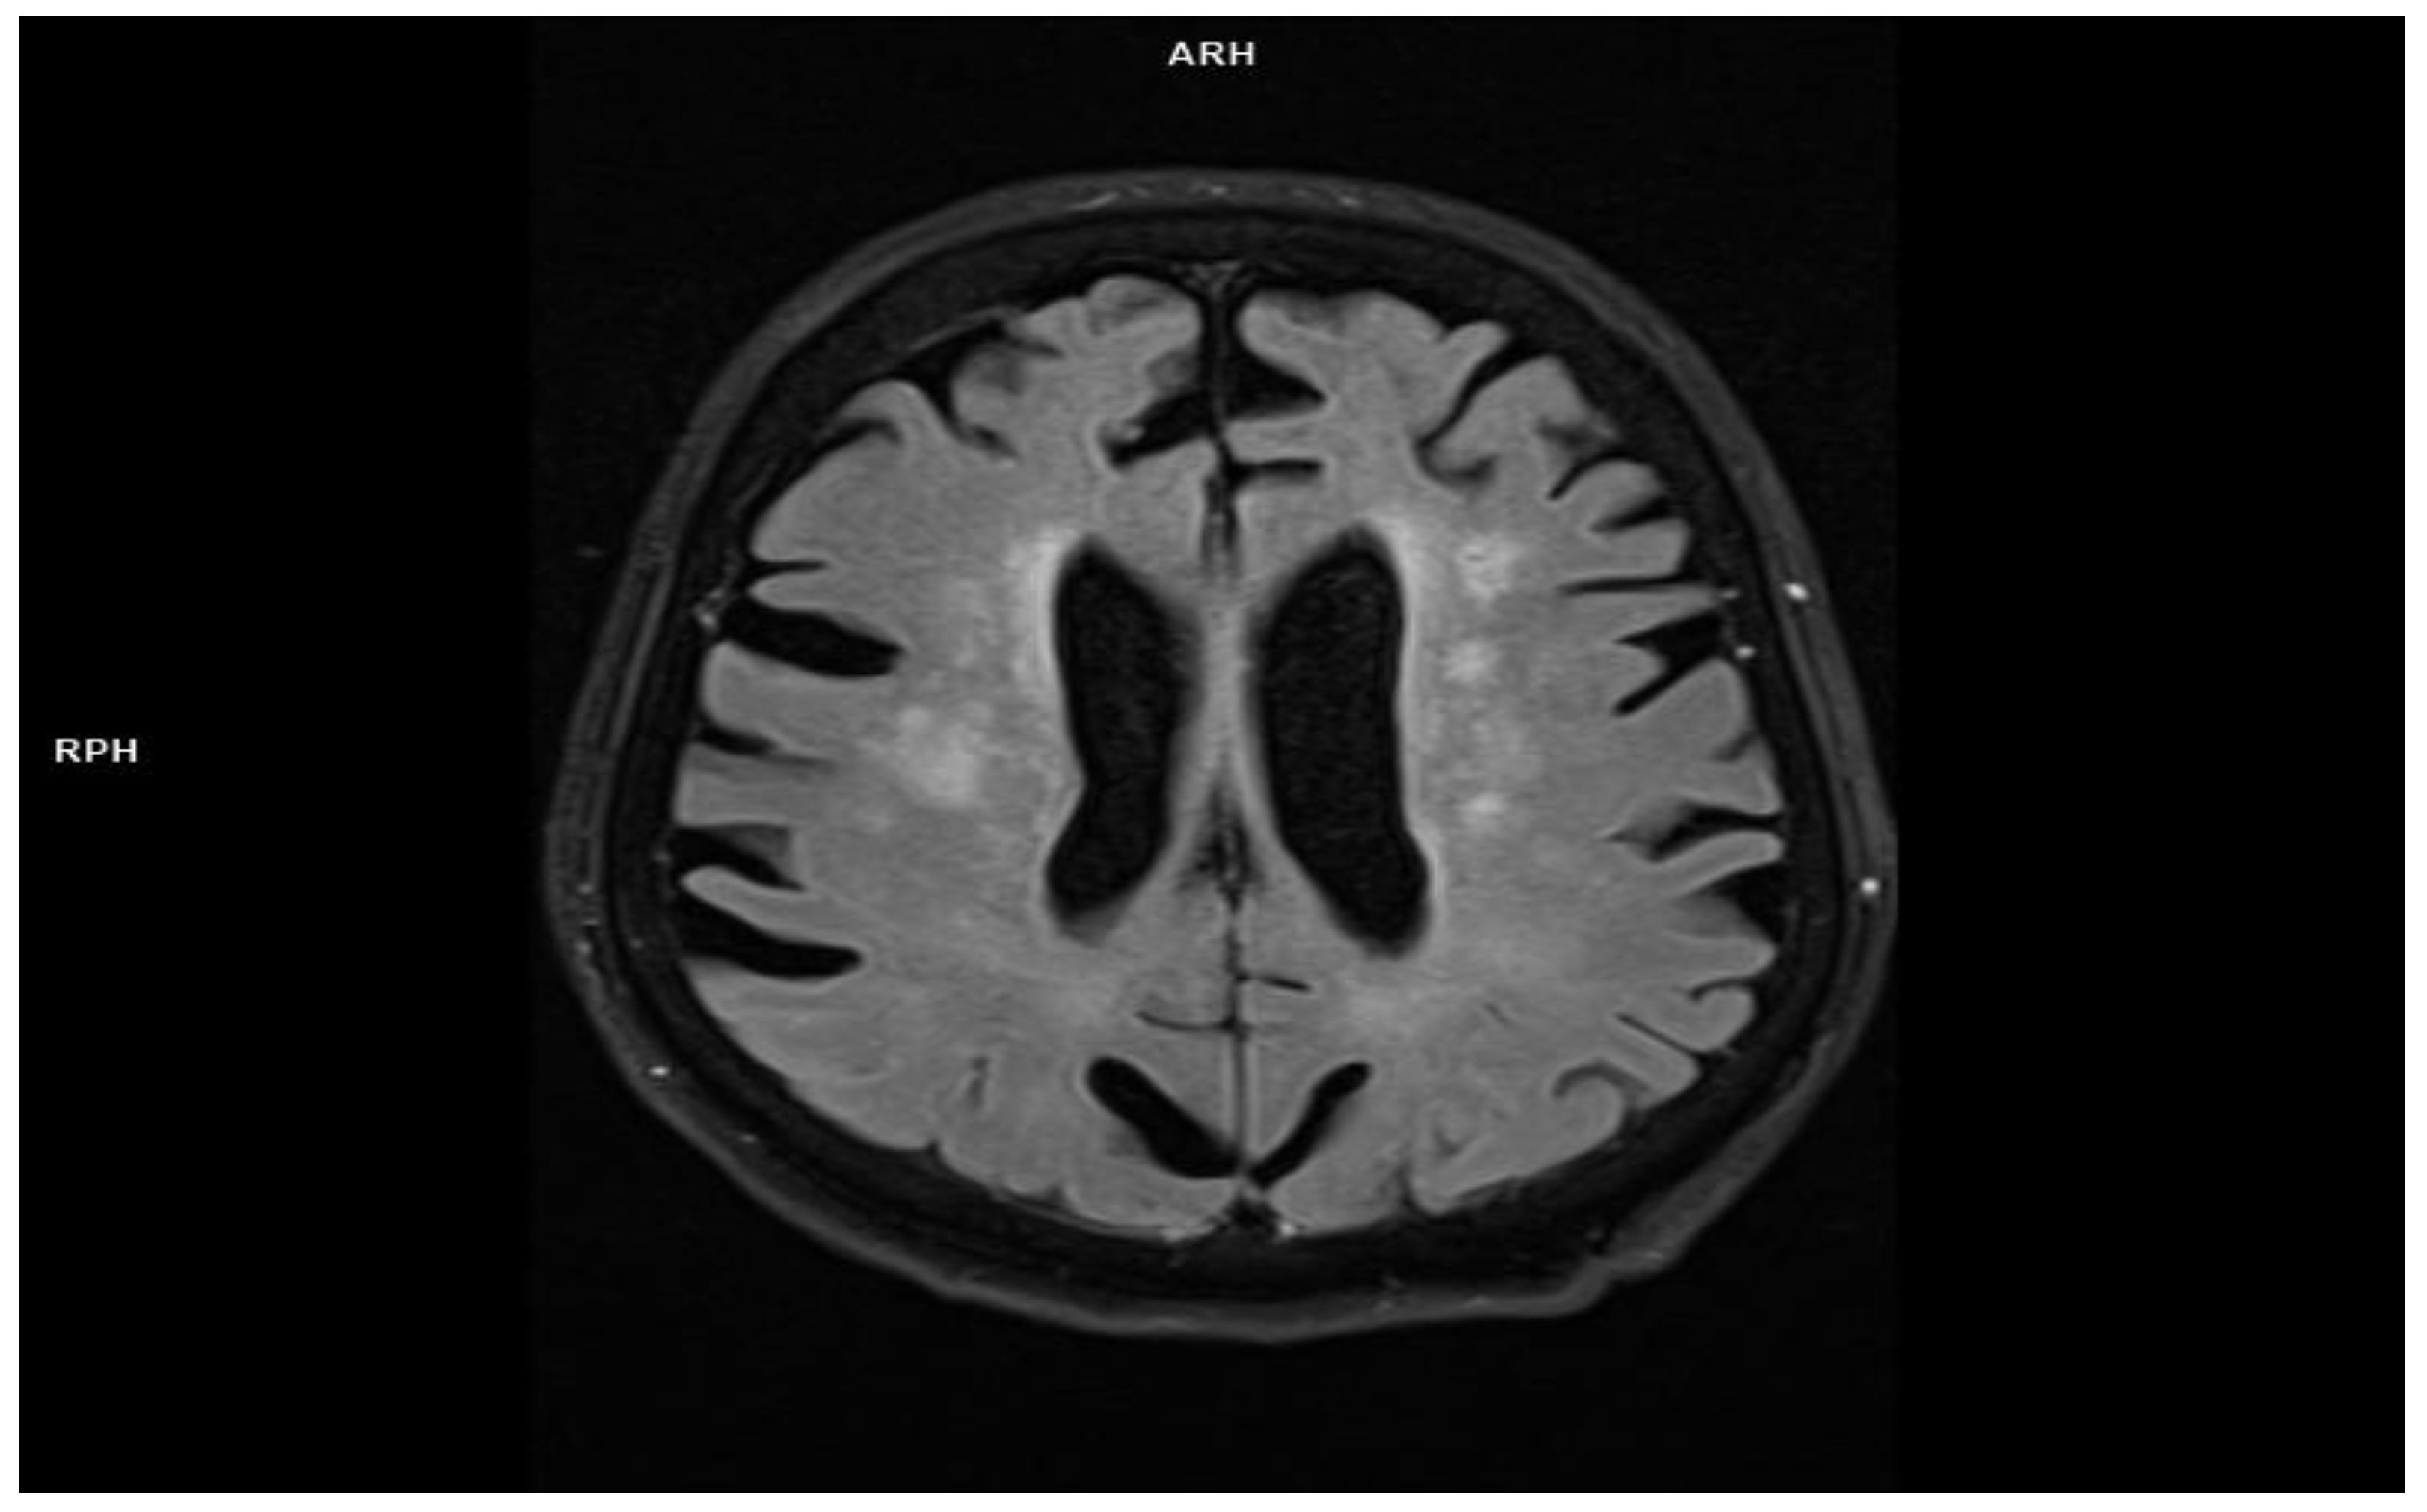

2.3. Patient 3